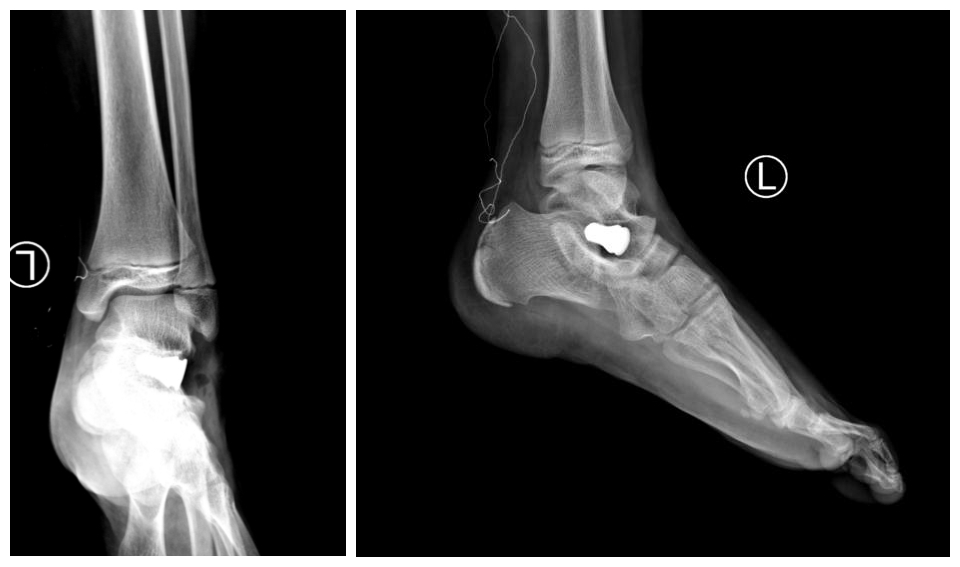

过去治疗平足通常采用软组织和骨的重建手术方式,但此术式创伤大、疗效差、并发症多,使很多医生遇到这种病例非常棘手。如今,国外的临床研究证实,距下关节跗骨窦螺钉制动术在儿童及青少年可复性平足的治疗中取得了非常满意的效果,跗骨螺钉是一个特别的骨关节内部置入物,它是由医用钛合金制造,并且简单轻松的放入踝与脚后跟之间自然存在的空隙间,一次手术就可以恢复健康,且运动不受限制。

近年来,国内逐渐采用此种手术,其创伤小、并发症少、疗效较确切。随着我院骨科专业化的发展及与国内外的积极探索交流,近期骨科四病区开展了省内首例距下关节跗骨窦螺钉制动术,手术非常成功,患者术后恢复好,效果满意。此例手术的开展标志着我院骨科在足踝外科领域已达到国内先进水平。